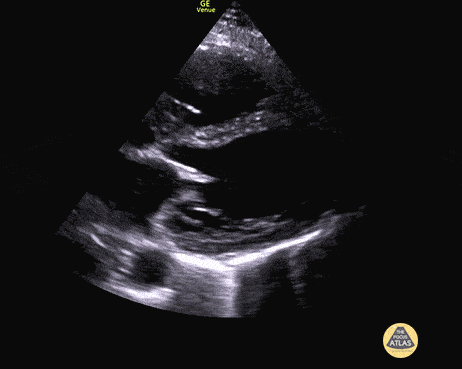

Left Ventricular Dysfunction - Biventricular Failure Parasternal Long

50 y/o M PMH methamphetamine abuse presents in respiratory failure with cool, mottled skin and poor capillary refill. Patient was tachycardic, hypothermic with multiple signs of end organ dysfunction. POCUS quickly narrowed the differential by demonstrating clear, severe, reduced ejection fraction by visual estimation and a plethoric IVC without respiratory variation. Patient was ultimately started on dobutamine and transferred to the MICU for treatment of cardiogenic shock. Dr. Jaclyn Walker, Dr. Matthew Riscinti - Denver Health Emergency Medicine